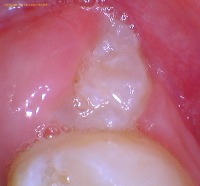

This is a real intraoral picture of a wisdom tooth with a huge cavity, which resulted in an actual hole in the tooth. You can see a large piece of the tooth structure is missing due to the cavitation.